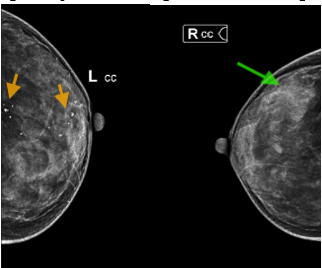

Hình 1. Vài nốt vi vôi hóa rải rác (mũi tên vàng). Đám tăng đậm độ bất đối xứng ở vú phải (mũi tên xanh)

– Chụp XQuang tuyến vú: Vài nốt vi vôi hóa trung tâm rải rác hai vú – BIRADs 2. ¼ trên ngoài vú phải có đám tăng đậm độ bất đối xứng kích thước 30x33mm – BIRADs 3.